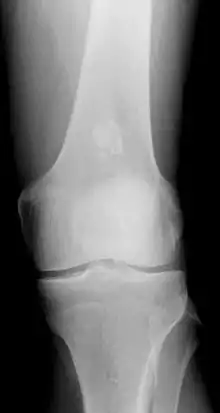

- x-ray – On plain film, an enchondroma may be found in any bone formed from cartilage. They are lytic lesions that usually contain calcified chondroid matrix (a "rings and arcs" pattern of calcification), except in the phalanges. They may be central, eccentric, expansile or nonexpansile.

Differentiating an enchondroma from a bone infarct on plain film may be difficult. Generally, an enchondroma commonly causes endosteal scalloping while an infarct will not. An infarct usually has a well-defined, sclerotic serpentine border, while an enchondroma will not. When differentiating an enchondroma from a chondrosarcoma, the radiographic image may be equivocal; however, periostitis is not usually seen with an uncomplicated enchondroma.